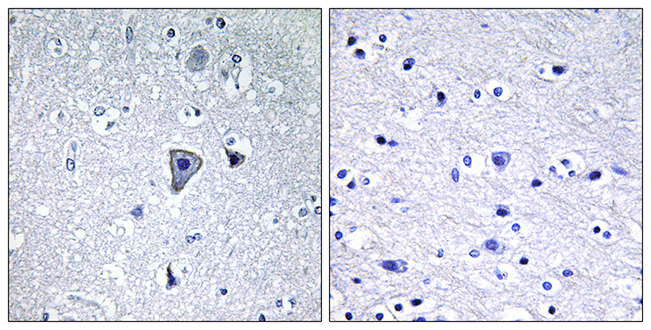

Anti-MNK1 AntibodyA97778

ApplicationsELISA, ImmunoHistoChemistry

ReactivityHuman, Mouse, Rat

Anti-MLK3 AntibodyA97779

ApplicationsELISA, ImmunoHistoChemistry

ReactivityHuman, Mouse, Rat